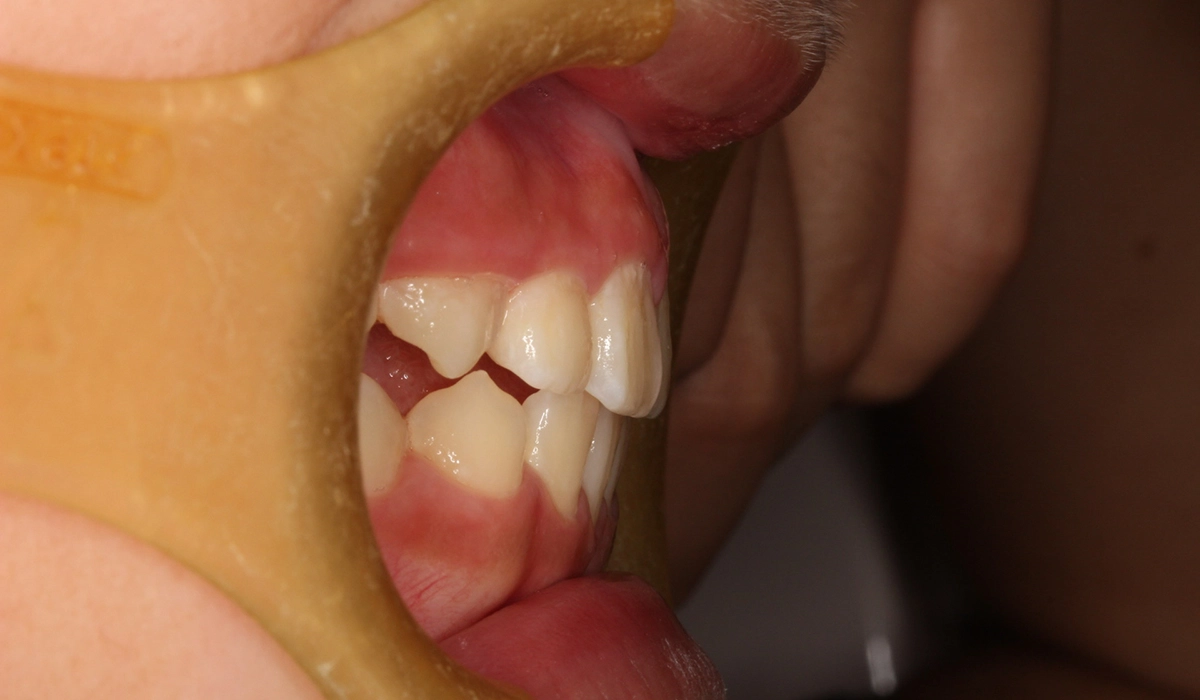

術前:右側